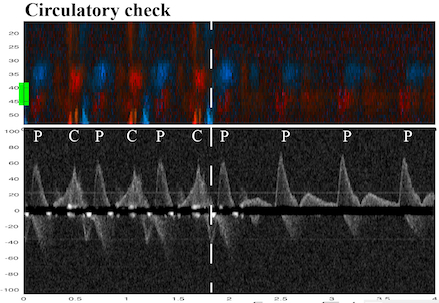

Methods: We used a porcine cardiac arrest model to investigate the RD. The RD probe was positioned and fixated over the carotid artery. An invasive blood pressure catheter was inserted in the contralateral carotid artery. An implantable cardioverter defibrillator (ICD) was utilized to induce sequences of ventricular fibrillation followed by defibrillation and chest compressions (cardiac arrest sequences). Compressions were administered manually at a rate of 100 or 50 compressions per minute or using a mechanical chest compression device (LUCAS). Doppler blood flow velocity curves were retrospectively analyzed for signs of ROSC by examining both spontaneous and/or compression-generated velocities (Fig. 1,2). We combined color M-mode and Doppler spectrum (Fig. 1) to differentiate between chest compression and spontaneous velocities.

Results: Data from eight animals (mean weight 30 kg) and 56 cardiac arrest sequences were included. In the analysis, chest compressions were identified as tissue movements through the whole spectrum of the color M-mode, in the spectral display (Fig. 1), or both. Spontaneous velocities were identified in a specific carotid depth of the color M-mode and between compression-generated peak velocities in the Doppler specter (Fig. 1). ROSC was confirmed by pausing chest compressions and evaluating ECG and invasive blood pressure. We identified spontaneous circulation during manual and mechanical chest compressions in 55 of 56 sequences.